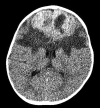

Fig 1.

Noncontrast CT, axial image, reveals a large predominantly hyperattenuating parafalcine mass with central low attenuation, extending to the frontal convexity, exhibiting mass effect and associated vasogenic edema.